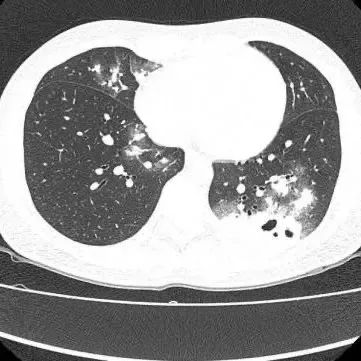

胸部CT显示其双肺多发感染

伴多发空洞形成

医生查房时,捕捉到CT上形似“鬼脸”的特殊影像(即“鬼脸征”),并伴有“晕轮征”,高度怀疑隐球菌肺炎。医生追问夏女士近期是否曾接触鸟类、禽类及饲养宠物,夏女士否认。

在影像学表现方面,典型CT表现是单发/多发结节伴“晕轮征”,结节液化坏死可形成空洞形似“鬼脸征”,空洞常为薄壁空洞、无液平。